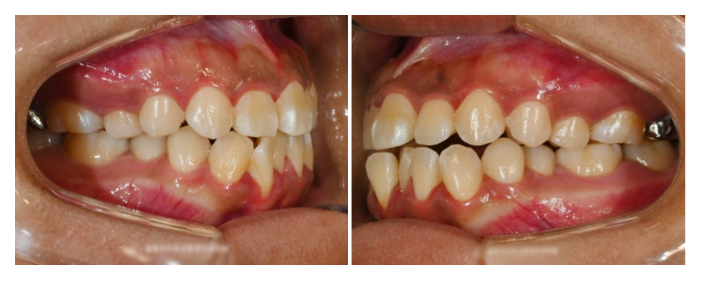

그리고 실제 구내를 살펴보면,

아래 전치부 쪽으로

총생(Crowding)을 찾아볼 수 있습니다.

총생이란 치아가 지나치게 밀집되어

자라난 상태로 배열이 올바르게 되지 않고,

서로 겹치거나 뒤틀려 있는 형태로

문제가 생긴 것을 말합니다.

초기에 심했던 Crowding은

깔끔히 정리되었으며,

치열도 가지런해졌습니다.